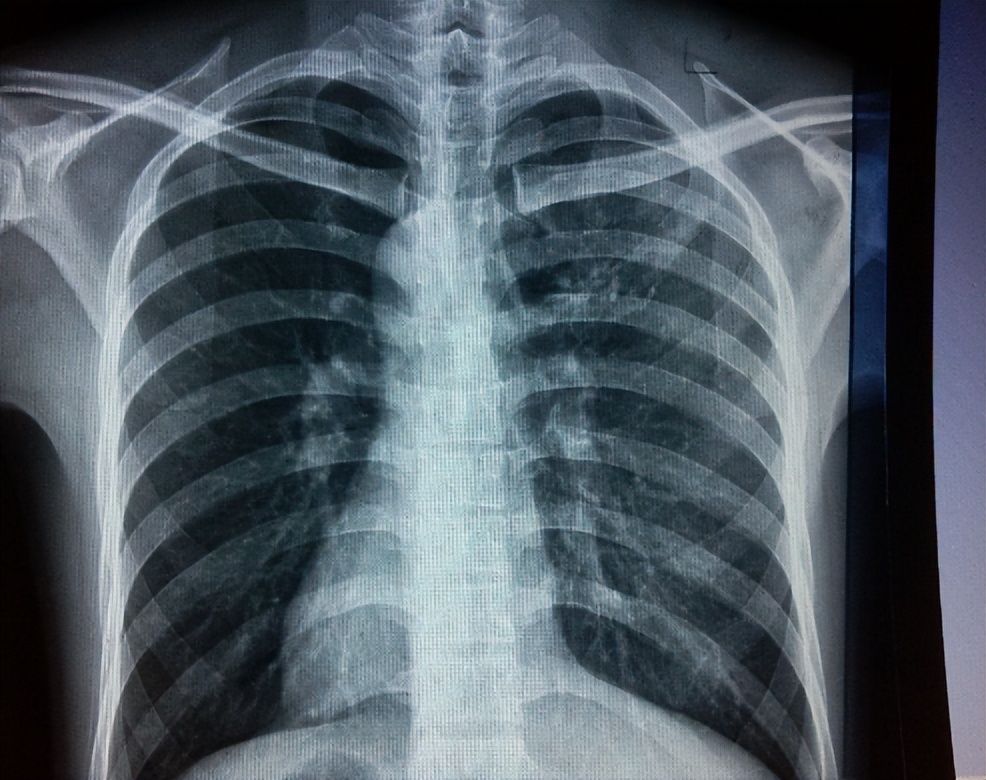

肺栓塞是由于肺动脉或其分支被血凝块或其他物质阻塞导致肺部缺血缺氧引起的尖锐胸痛。

通常伴有呼吸困难、咳嗽、咯血、发热等症状,并且在深呼吸或咳嗽时加剧。

肺栓塞可能由于长期卧床、久坐、手术、怀孕、避孕药等原因引起。

医生可能会给我们做超声波检查或X光检查,以确定胆囊是否有炎症或结石,并给我们开一些抗生素或止痛药。